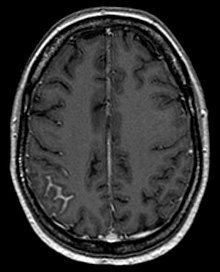

L'analyse des cellules dans le liquide cérébrospinal lors d'une ponction lombaire peut faire le diagnostic mais nécessite parfois d'être répétée[3], l'absence de cellules suspectes se voyant dans un quart des cas[4]. L'IRM cérébrale peut également aider[5].